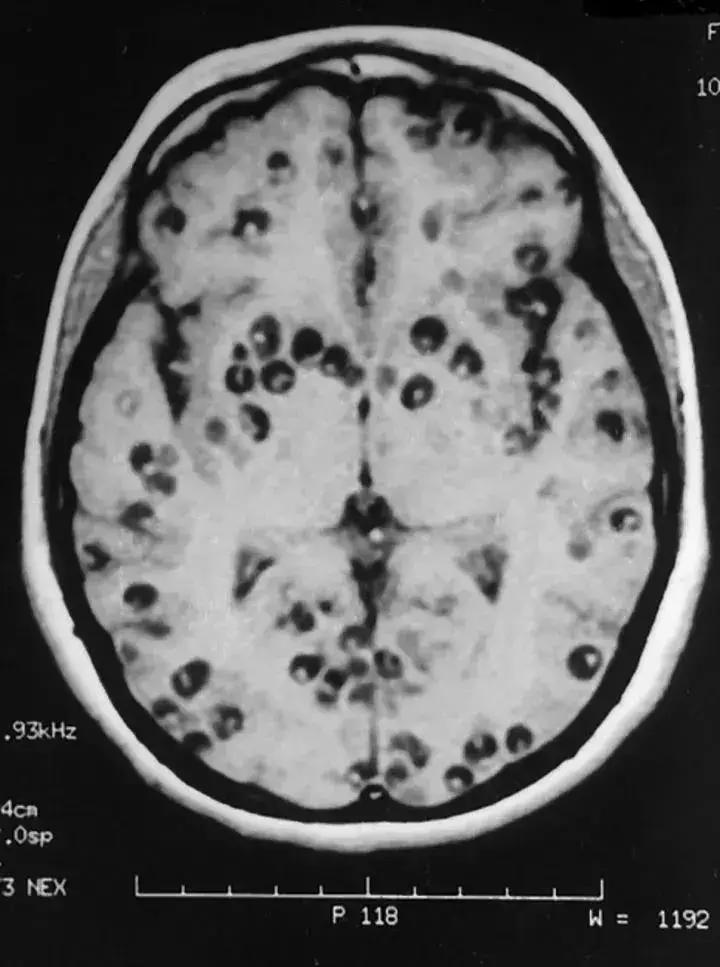

最严重最常见的还是脑囊虫病,占了囊虫病的80%。囊虫进入到脑部,首先会压迫脑组织,造成炎症、水肿等。严重会使人产生明显的神经障碍,甚至死亡。

点状物即为囊虫